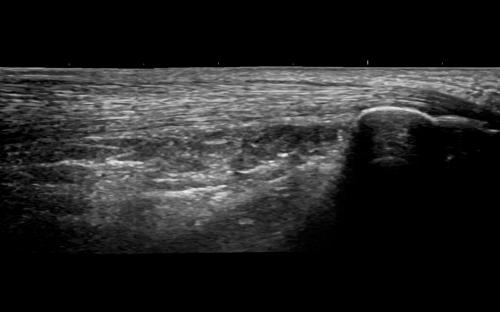

查看完整图像 超音频多功能图像系统 弗尼泽: 通用电气医疗 分类: 超声造影 水平标签 描述 凡尔赛那平衡是一个多功能生态系统,用于完成腹部检查、产科工程、口腔、肌肉、血管、泌尿、儿科和心脏病的检查。 Av和un设计工效学-现代、环保的成人能力-卓越的稳定性-诊断、快速、精确、分散和功能变化: 乳房护理/甲状腺生产力-分析模块,特别是在不同类型的系统中 B-流量-独立于生态技术的多普勒利用率评估血管结构 自动IMT-网络媒体自动管理模块 针识别-生物程序的虚拟化模块 自动EF-分析心脏变形的仪器,用于分析心室破裂的结石 Mod de analiză4DVizaliza toate cele 3 planuri ale structurilor Anomologie,av–and Utiliteîn specialîn aplicațiile de Occomaticăi de ginecologie 想象临床 查看完整图像 查看完整图像 查看完整图像 查看完整图像 德斯卡ă 描述: 韦尔萨纳兄弟天平 韦尔萨纳兄弟家族 教育 通用平台是一个可持续发展的教育支持平台,它是一个可持续发展的生态系统的应用平台,它是一个信息产业的发展平台,也是一个医疗实践的平台,在Versana ecografele中,阿替卡因和阿替卡因是一种具有丰富经验的药物。 特别是注册简单的VersanaClub depăeșeșe Barirele de timpși spași uneșutilizatori de ecografe Versana pentru联合国医疗卫生标准法案。 联邦登记局链接:https://www.versanaclub.net/ 视频 凡尔萨纳平衡:胜任。有效率的实际的 Versana Balance视频:胜任。有效率的实际的 特别条款: ATI 心脏病学 奇鲁吉将军酒店 内分泌学 家庭医学 麦地那 内科医生